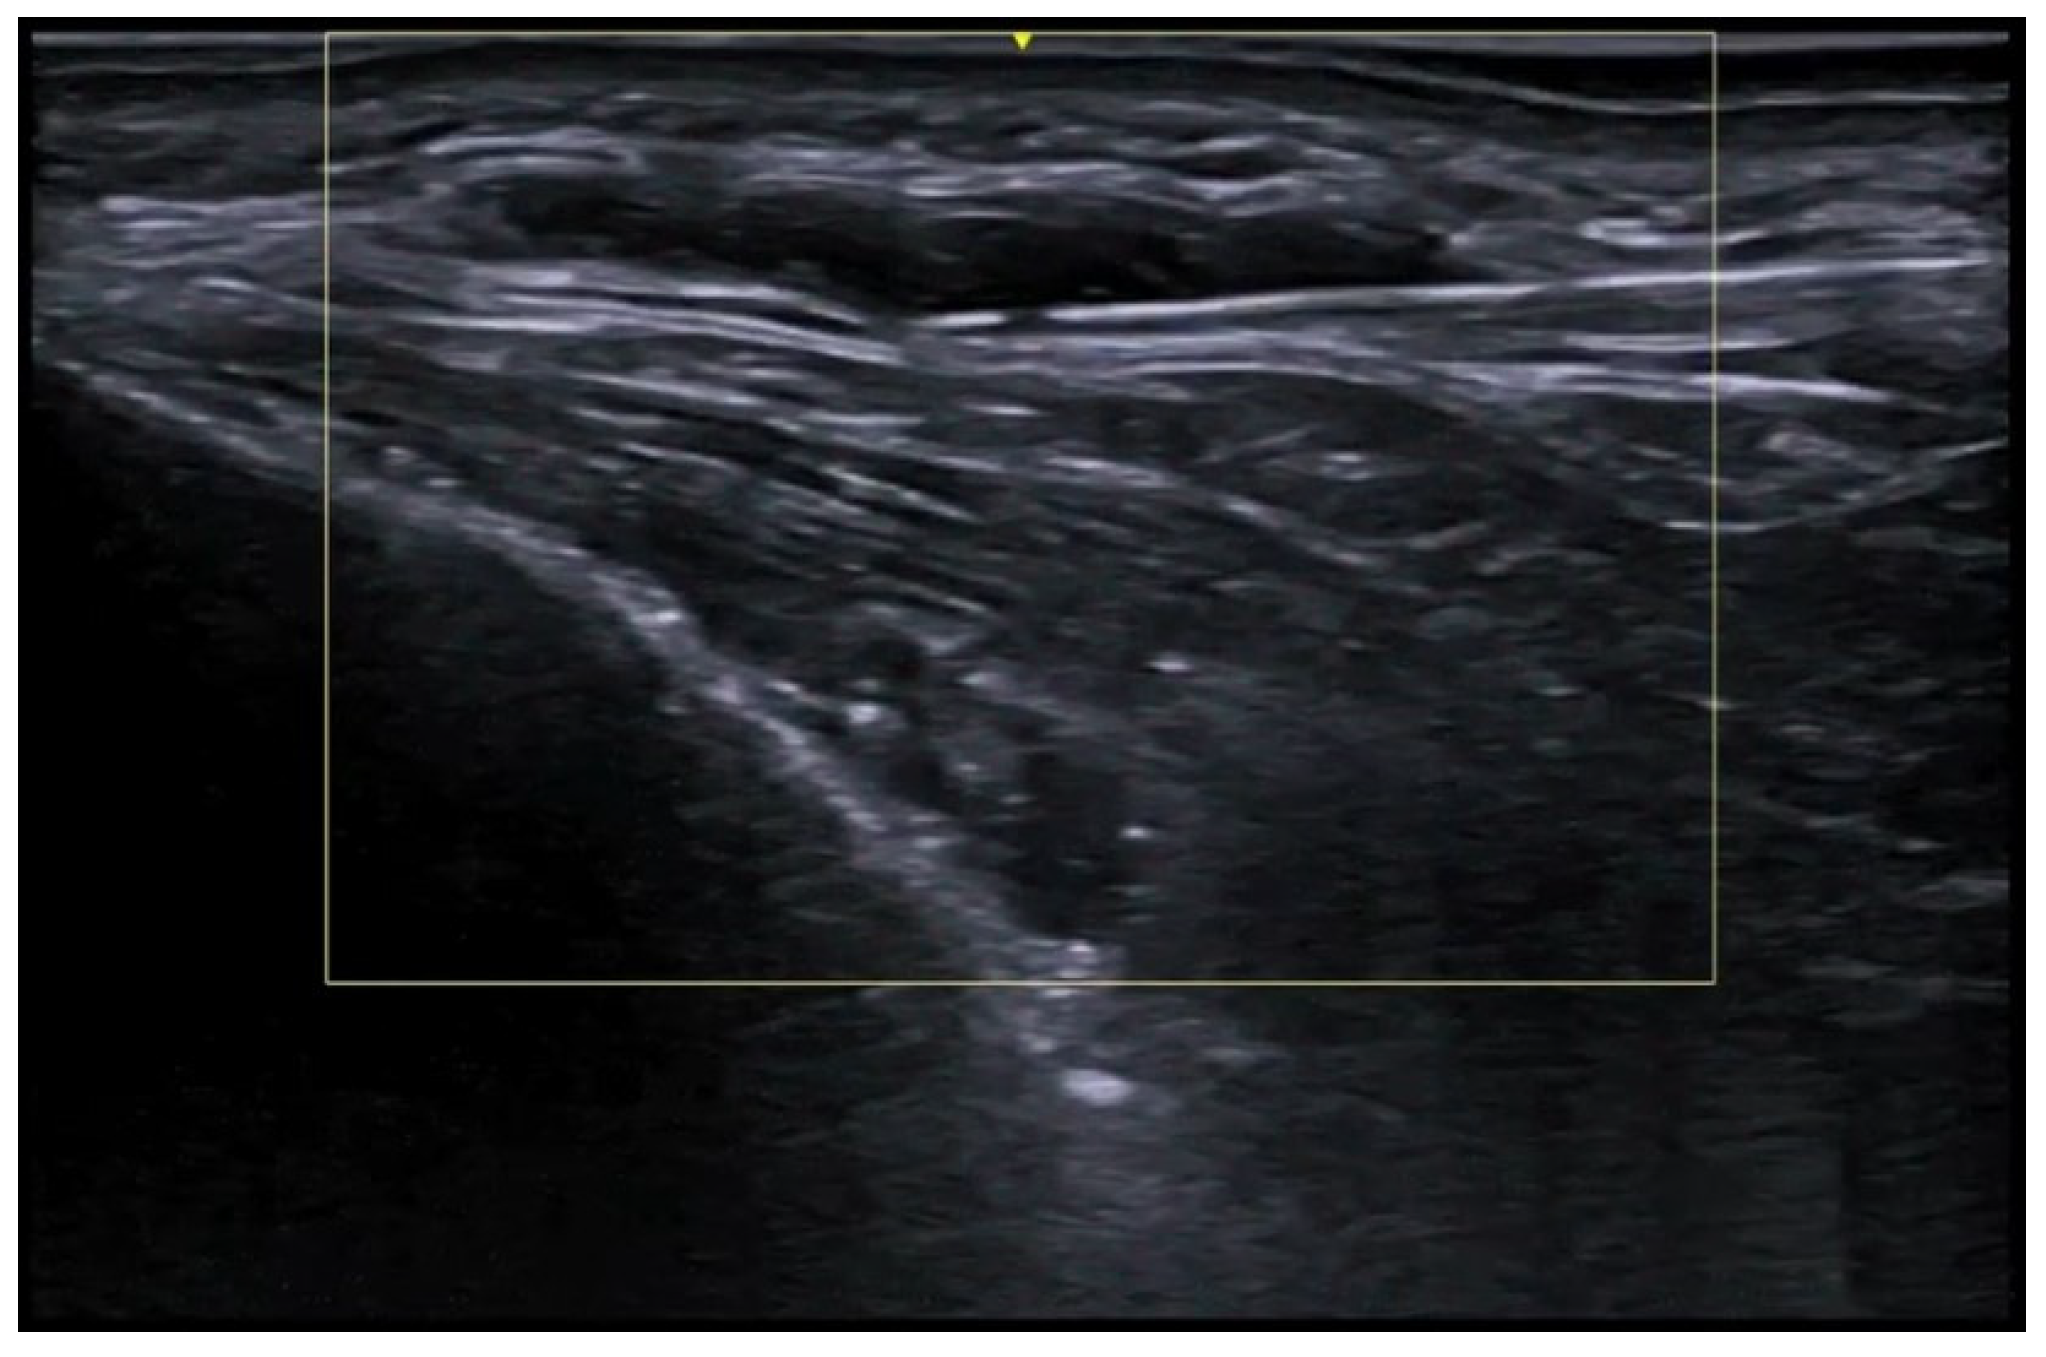

7. External-Agent-Associated Disorders

8. Neoplastic Diseases